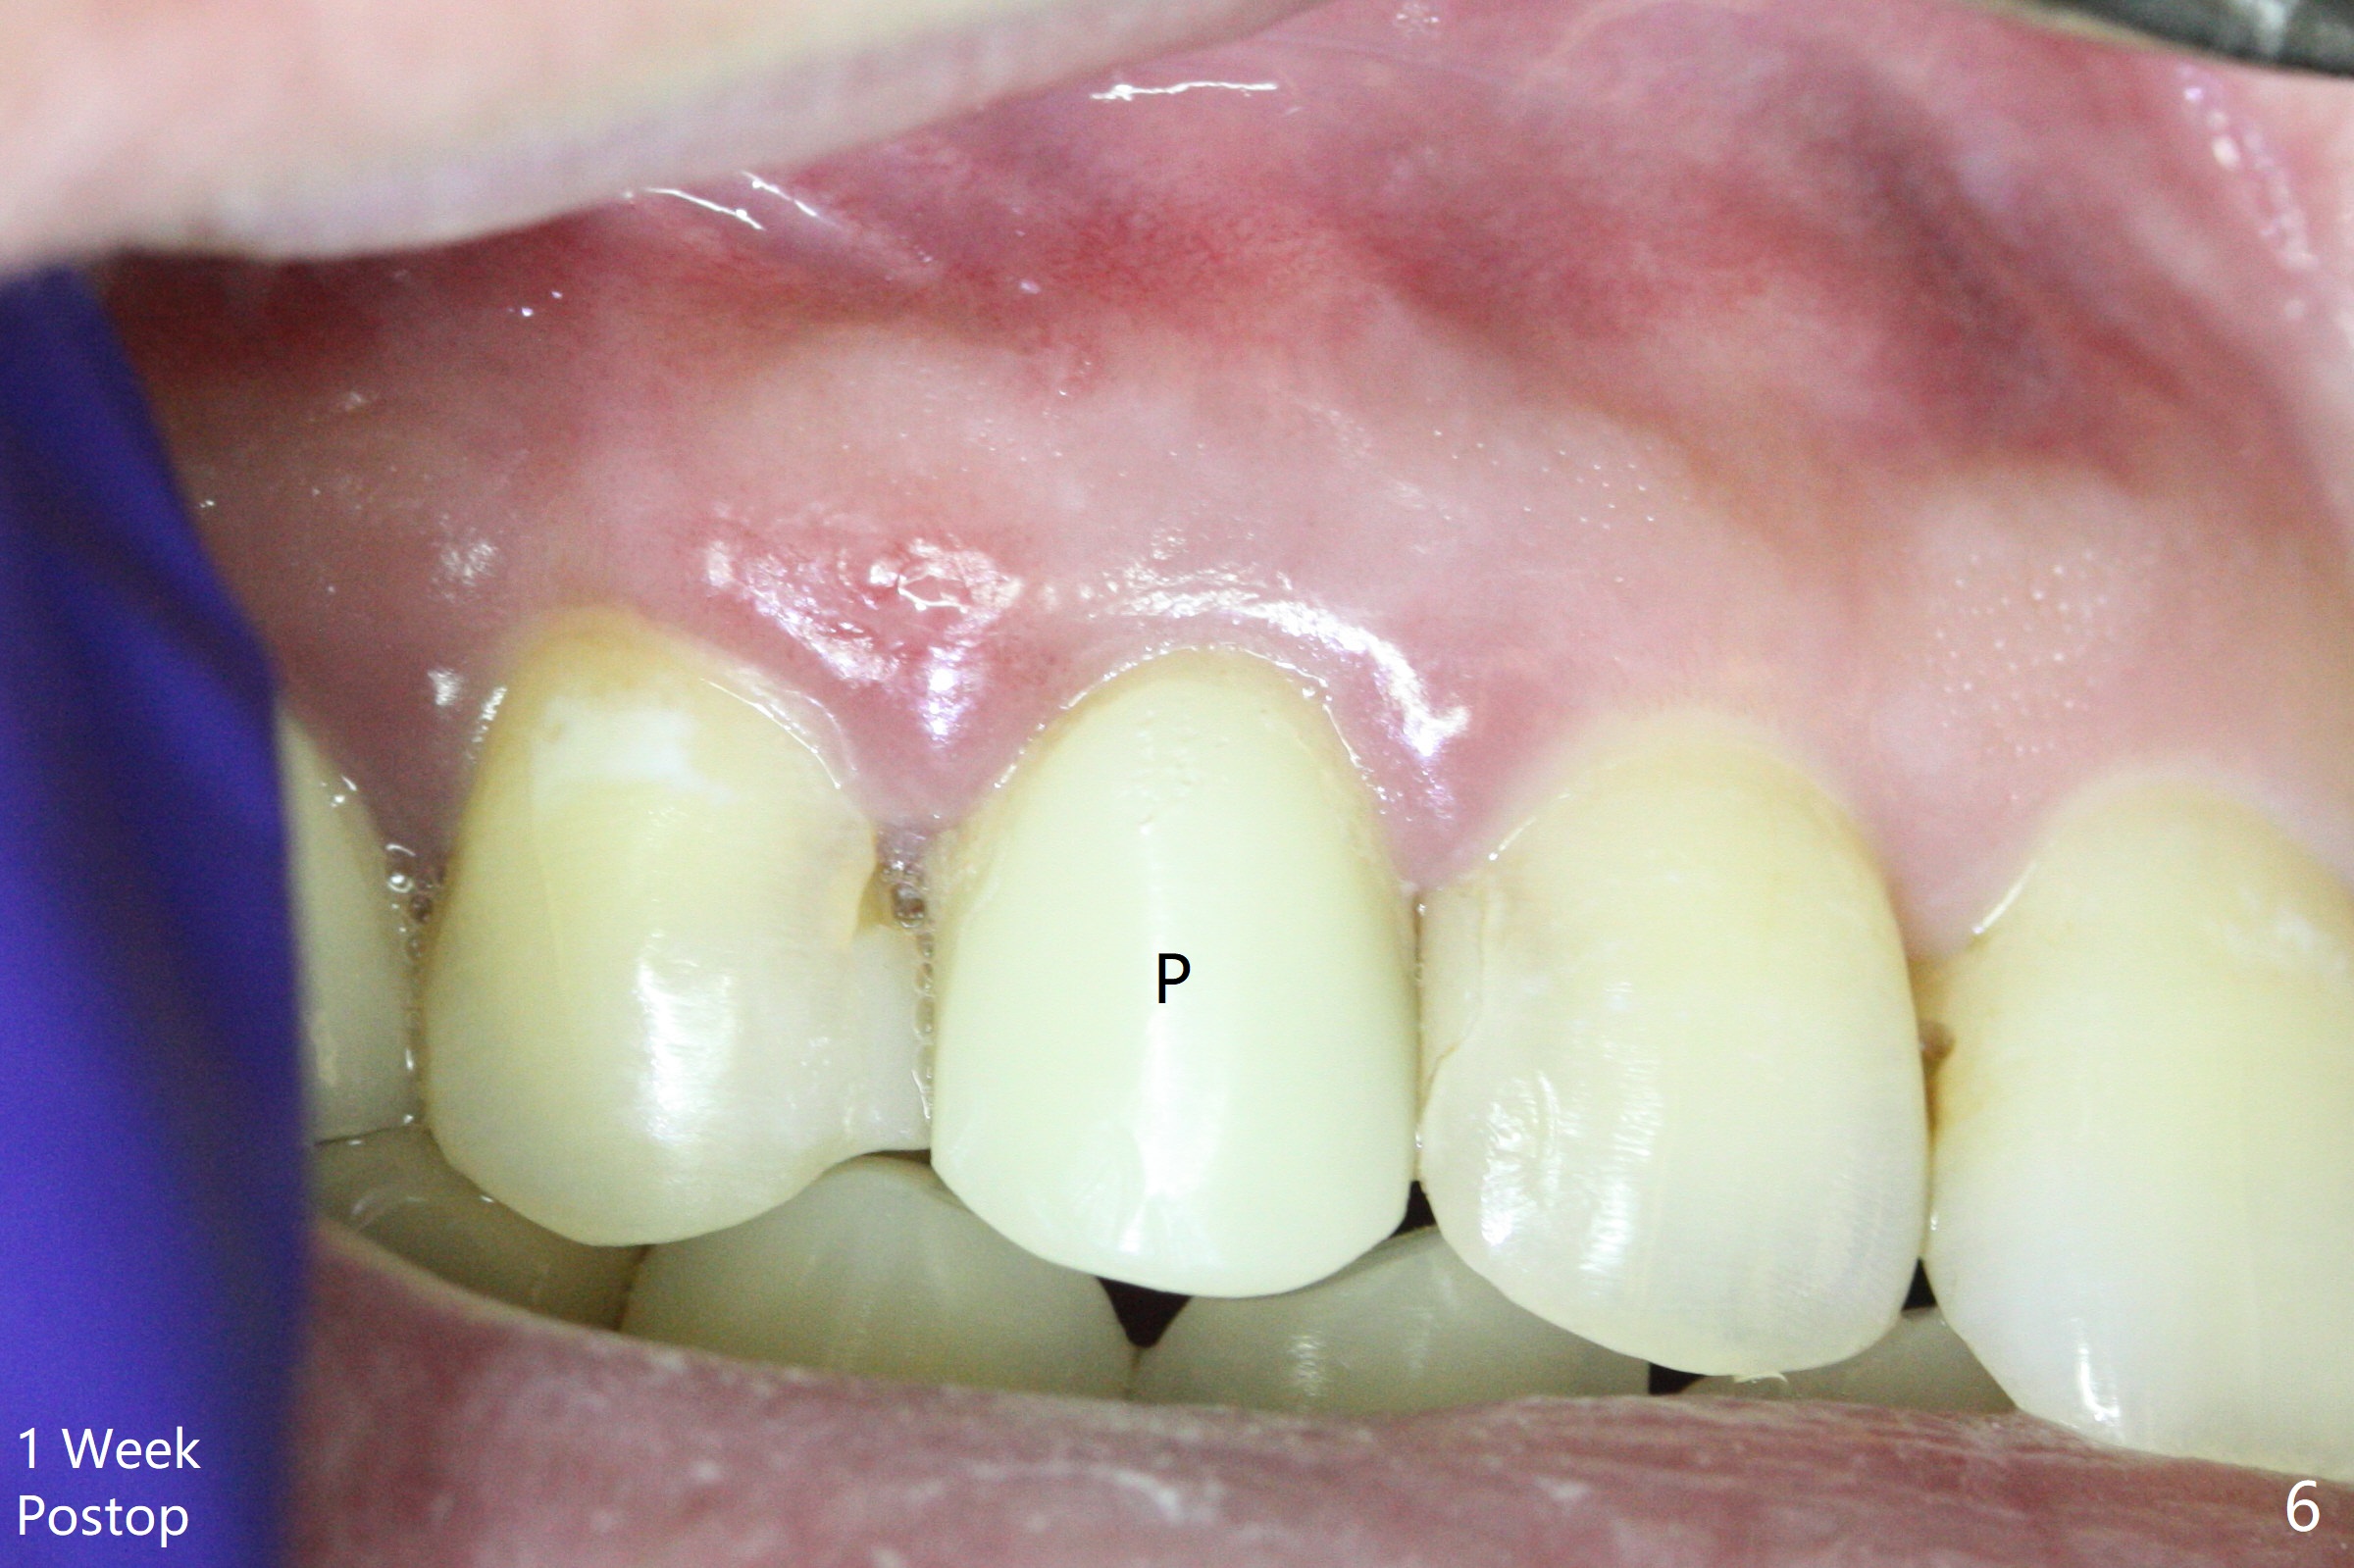

When the tooth #6 with loose crown and post (Fig.1) is extracted, there is no granulation tissue in the socket with the thin intact buccal plate. As planned, osteotomy is initiated in the mesio-palatal slope of the socket (Fig.2 red dashed line). After osteotomy for 3x20 mm (gingival level), a 3.8x15 mm dummy implant is placed partially (Fig.3 D). A final implant with the same dimension is placed with > 50 Ncm (Fig.4). Before and after placement of a 4.5x5(3) mm abutment, Vera graft is placed in the remaining socket space (mainly buccal, Fig.5 *). As routine, an immediate provisional is fabricated with occlusal clearance. The gingiva looks healthy around the provisional 1 week postop (Fig.6 P). Adjust and polish the mesioocclusal composite at #5 if necessary before impression. The bone graft appears to remain in place 4.5 months postop (Fig.7). A bevel buccal subgingival margin is placed prior to impression. The bone density around the coronal portion of the implant increases 9 months postop (4 months post cementation, Fig.8). There is no gingival erythema or edema around the implant crown at #6 ten months post cementation (Fig.6, as compared to preop condition and that of the neighboring crown (*)). Both the buccal and palatal plates are thin or absent 1 year 5 months post cementation (Fig.10,11, as compared to Fig.12 for the tooth #11 (thin buccal bone)). Socket shield should be done with a smaller implant.